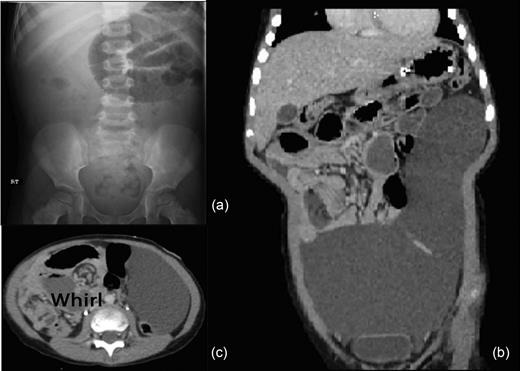

A 4-year-old previously healthy male presented to an outside hospital with 2 days of nausea and bilious emesis. An abdominal plain film (Fig. 1a) revealed small bowel obstruction and an abdominal ultrasound was nondiagnostic. Upon transfer to our institution, he had persistent bilious emesis with periumbilical abdominal pain. His medical and surgical history was unremarkable, with no history of antecedent trauma. His mother noted an increasing abdominal girth over the prior several months, but did not seek medical attention. On physical examination, the child's abdomen was soft, mildly distended and with periumbilical tenderness. He had no rebound tenderness or guarding, and no hernias were present. Review of the ultrasound revealed extensive intra-abdominal fluid. An abdominal computed tomography (CT) scan was obtained and revealed a large intraperitoneal cystic mass measuring 13 × 21 × 9 cm in the left abdomen (Fig. 1b). A small bowel obstruction was also present with concern for volvulus due to mesenteric swirl seen on axial imaging. There was no evidence of compromised intestine on CT (Fig. 1c). The patient was taken to the operating room for laparoscopy. The cyst, which arose from the mesentery of the small intestine, resulted in a segmental volvulus with congestion of the involved segment (Fig. 2a–c). A short vertical midline incision was made to allow the giant cyst to be delivered and the volvulus reduced. After reduction, the congested small bowel returned to a normal appearance. The cyst was excised by removing the 8 cm segment of small bowel from whose mesentery it arose (Fig. 2c). The abdomen was closed and the patient was discharged in excellent condition.

(a) Abdominal X-ray revealing small bowel obstruction in the left upper quadrant. (b) Abdominal-pelvic CT coronal image revealing 13 × 21 × 9 cm intraperitoneal cystic lesion. (c) Abdominal-pelvic CT axial image shows the classic whirl of mesenteric volvulus.